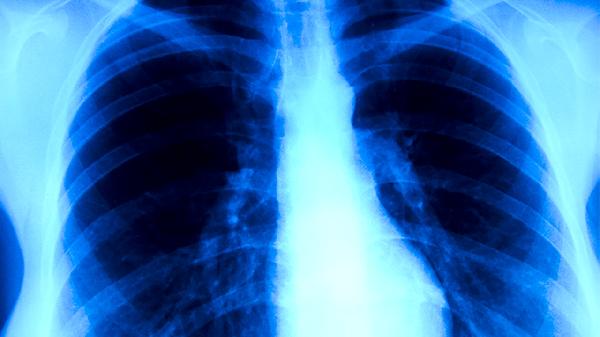

肺心病患者日常保养需结合生活方式调整、饮食管理和医疗监测,主要有戒烟限酒、规律氧疗、适度运动、控制盐分摄入、定期复查五项措施。